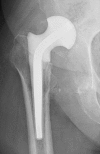

Two-stage revisions with antibiotic-loaded spacers have gained popularity for treating infected hip-joint arthroplasties. The aim of this prospective study was to assess patient functionality between stages and treatment impact on duration of hospital stay and to describe related complications. Sixty-one consecutive patients with infected hip arthroplasties underwent two-stage revision with preformed spacer implantation. Mean Harris Hip and Merle d'Aubigné scores between the two stages were 39.9 and 7.6, respectively. Forty-six patients (75.4%) were able to leave hospital between stages. Spacer dislocation occurred in 16.4%. No cases of spacer breakage were noted. Preformed cement spacers provide acceptable functional outcome between revision hip arthroplasty stages and facilitate the surgical procedure without increasing mechanical complication rates.